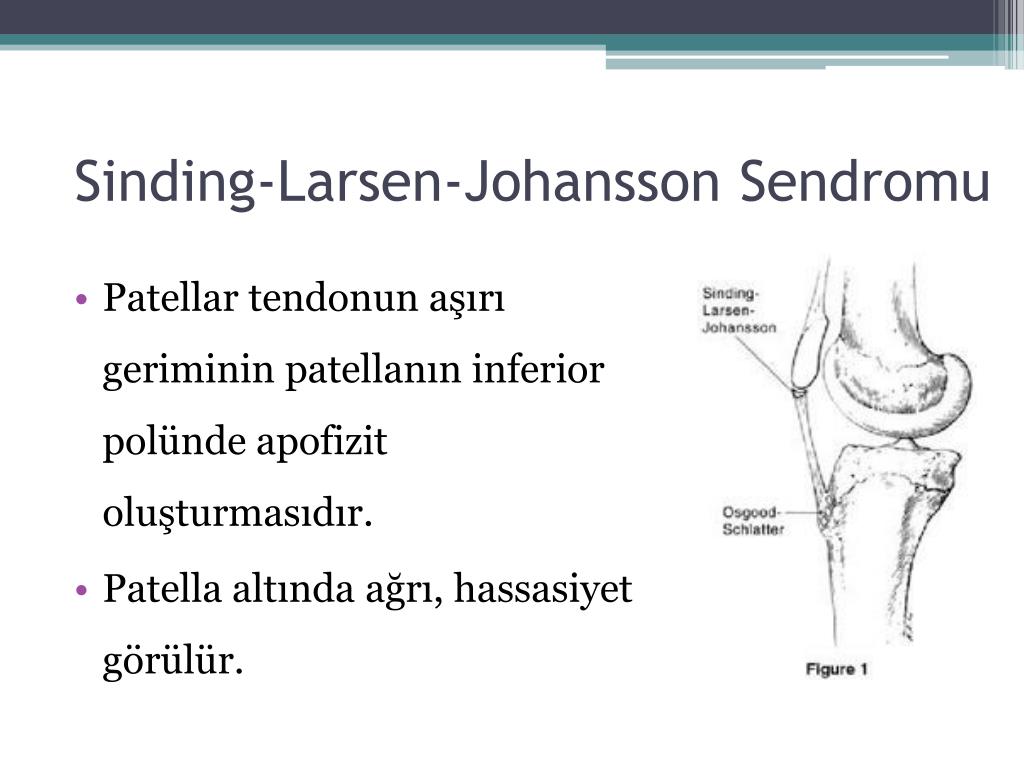

Ларсена йохансона

Ларсена йохансона 146 фото